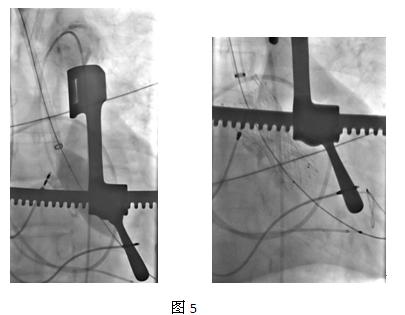

手术过程:术前动脉CT显示双侧髂股动脉弥漫性显著狭窄、钙化,管腔直径最小处仅为4.1mm(图1),因易导致严重血管撕裂、出血,故不宜经此路径实施TAVR。此外CT及血管造影亦显示左侧锁骨下动脉同样存在狭窄及钙化,亦不适合。分析患者的升主动脉解剖特点:长度及角度均适宜行TAo-TAVR,遂采用该路径(图2)。首先,全麻下有外科行约6cm胸骨正中切口(图3),暴露升主动脉后经升主动脉造影选择适宜的穿刺点,之后在主动脉壁穿刺点建立标准的荷包缝合,再置入14French鞘管,首先使用23mm×40mm Numed球囊行预扩张(图4),之后取出鞘管,直接经穿刺点送入输送系统,置入29mm VENUS 瓣膜,待完全释放后行升主动脉造影可见2/4级返流,经鞘管送入Numed 25mm×40mmNumed球囊实施后扩张,再次造影发现返流量无明显减少,遂选择28mm×40mm球囊再次后扩张,反流量减少为1/4级(图5)。遂缝合穿刺点后关胸。术后患者进入外科恢复室监护。12小时后患者清醒后转入普通病房。